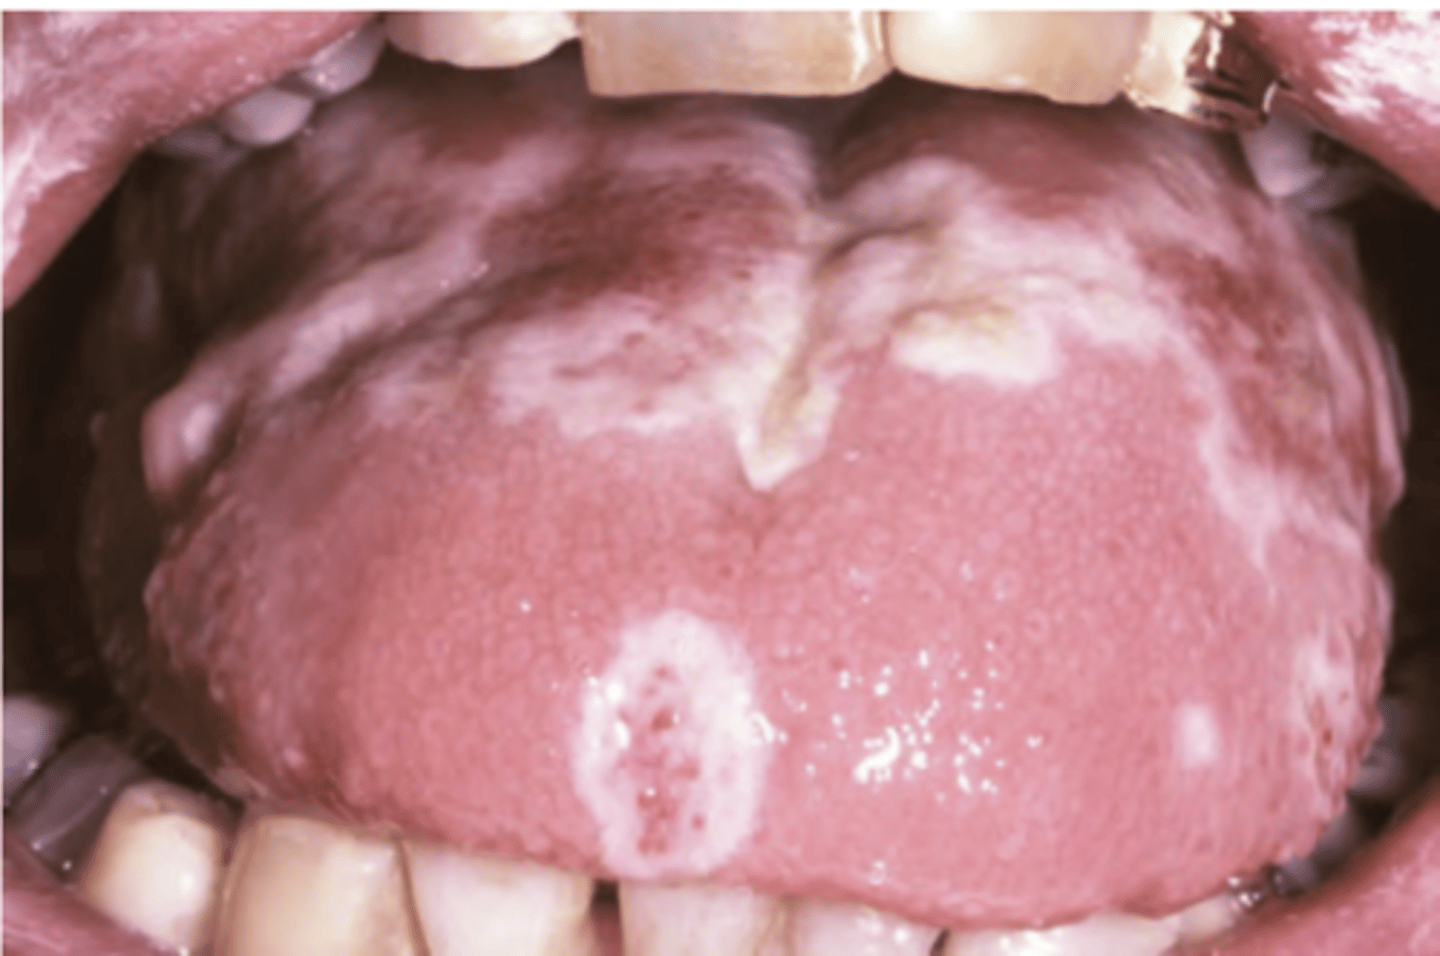

Pemphigus Vulgaris

Hint: Painful and long persisting superficial and ragged erosions affecting mucosal surfaces

Hint: Oral lesions are "First to show, last to go"

Hint: Flaccid vesicles & bullae that rupture quickly